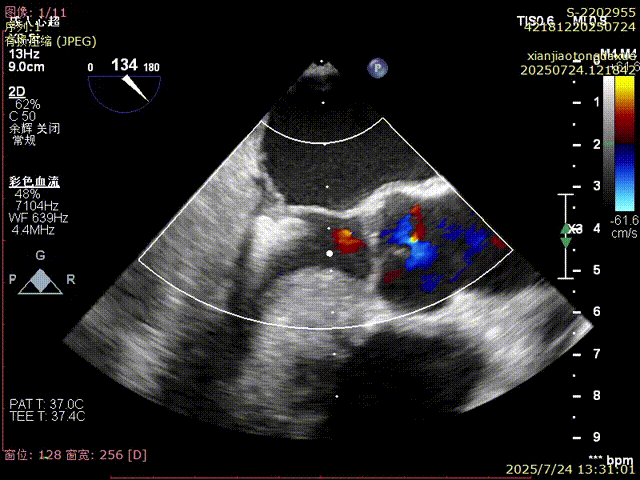

反流得到明显改善

3D视角下反流情况

术后夹合数据确认,达到预期效果